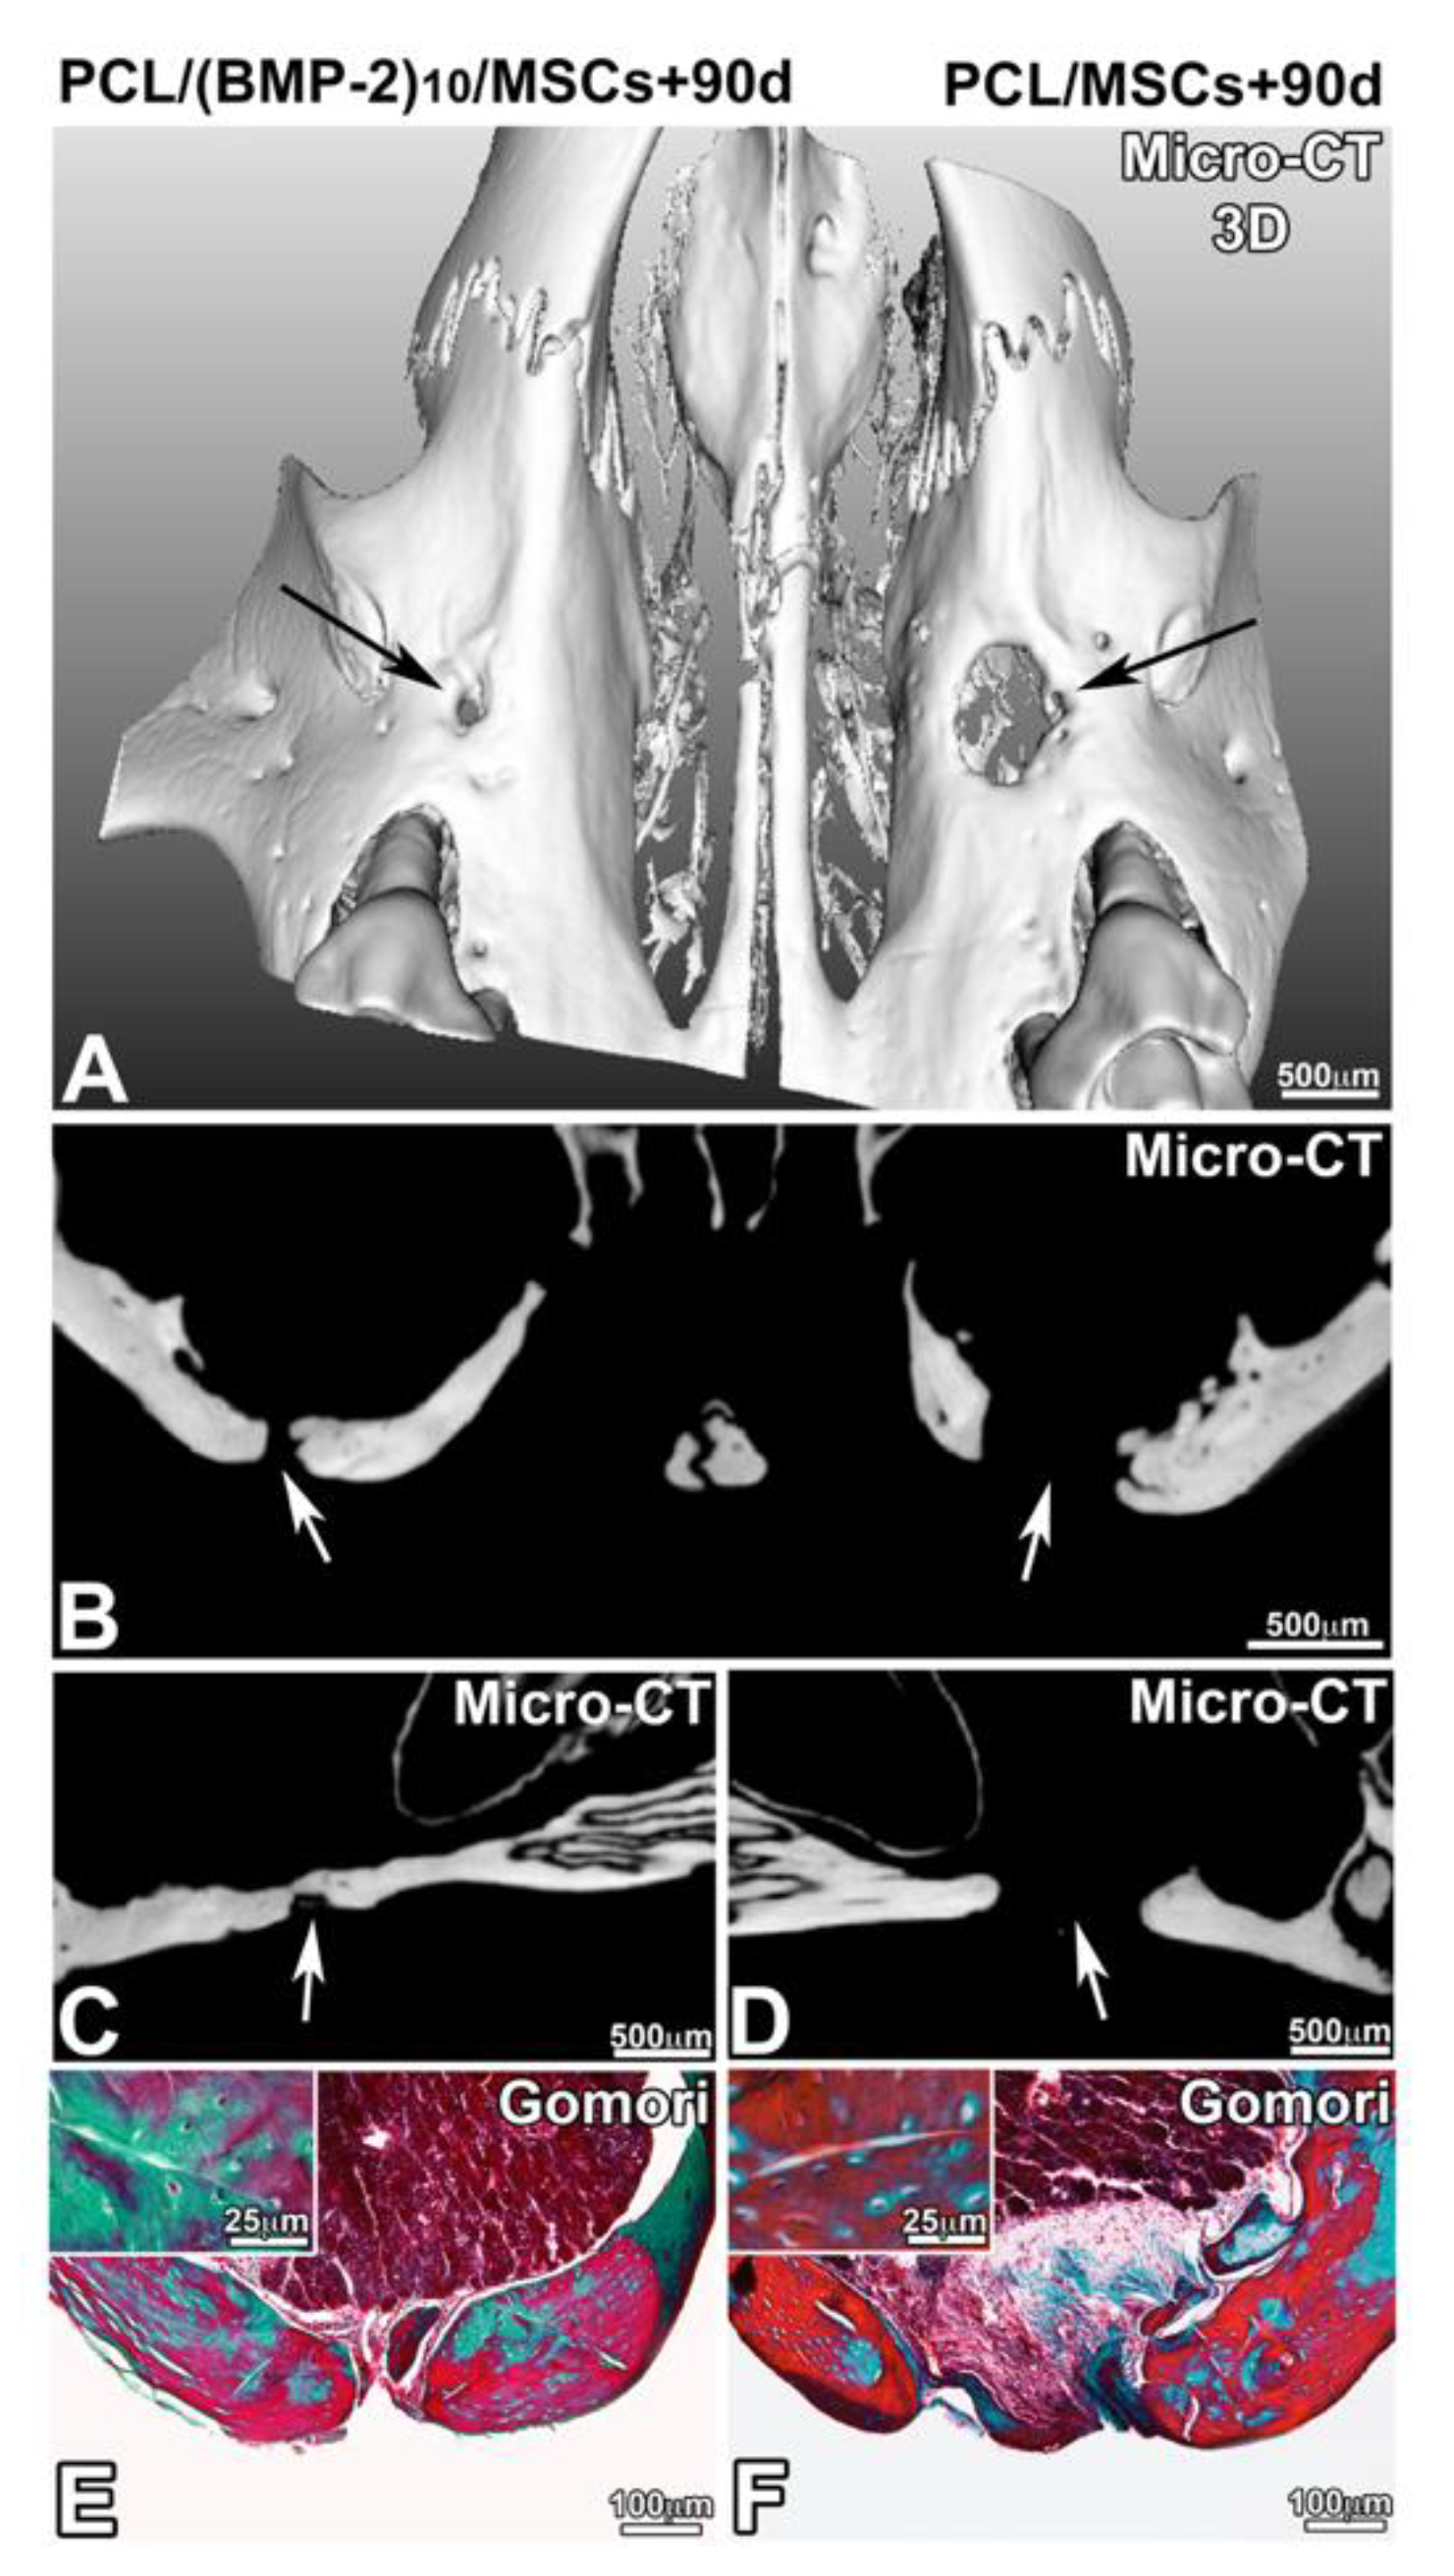

3.3. Maxillary Bone Regeneration